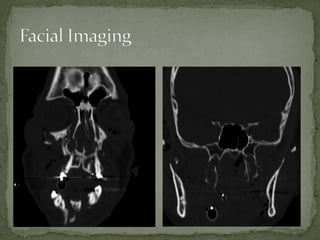

A 38-year-old man was found unconscious 40 yards from the scene of a motorcycle accident. He had obvious facial trauma including a midface fracture, severe facial edema, and blood in his oropharynx. His vital signs included a temperature of 98.6 F, heart rate of 120, respiratory rate of 12, and oxygen saturation of 90% on a nasal cannula with a blood pressure of 95/60. His Glasgow Coma Scale was 8. Imaging showed right type III and bilateral pterygoid fractures. He required intubation, ophthalmology consultation, and admission to the operating room for open reduction and internal fixation of his facial fractures.